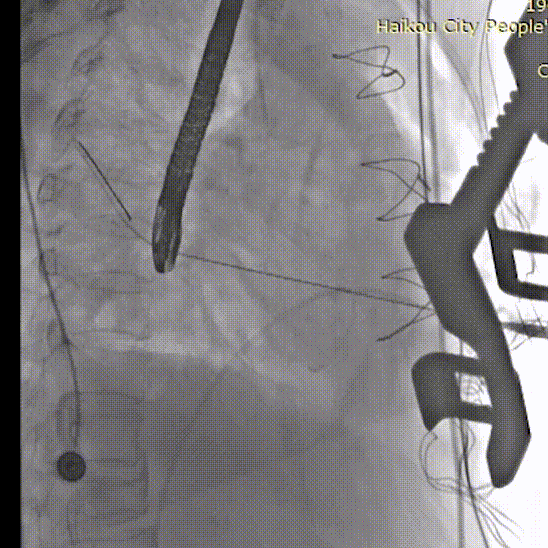

加硬导丝建立轨道,置入瓣膜输送系统

打开定位件,调整位置